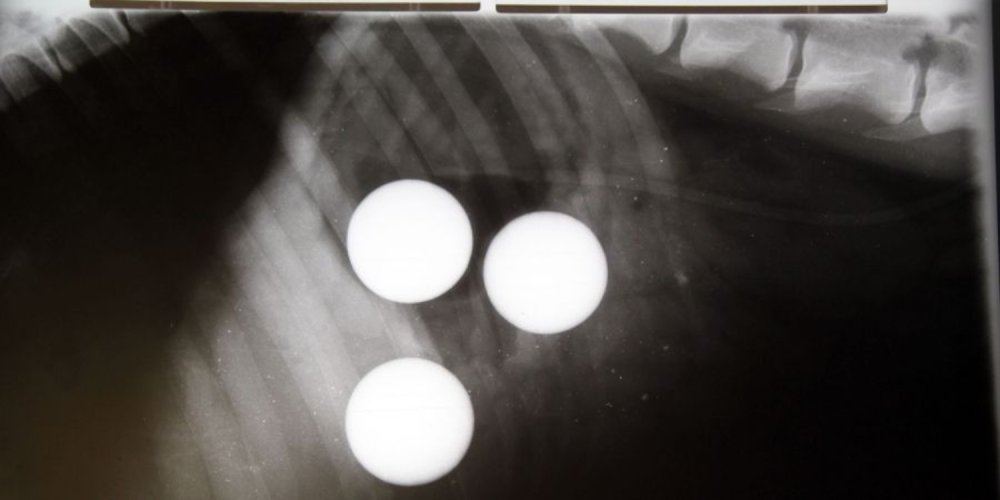

4. Žogice za golf

Če nameravate naslednji božič presenetiti prijatelja ali družinskega člana z darili za golf, bodite previdni v bližini radovednih hišnih ljubljenčkov. Ko je doberman Azar nenadoma shujšal, ga je njegova lastnica odpeljala k lokalnemu veterinarju. Na njeno presenečenje so odkrili, da ni pogoltnil ene, ampak kar tri žogice za golf! Na žalost sta se dve žogici zagozdili v njegovem tankem črevesju, zato je bila potrebna hitra operacija s katero so žogici kirurško odstranili.